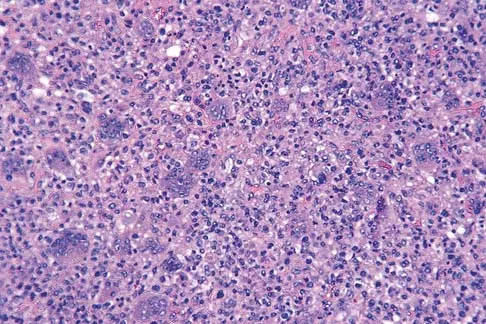

Question 55 High Yield

A 30-year-old patient has had severe left hip pain and difficulty ambulating, necessitating the use of a cane, for the past 6 months. A photomicrograph of the femoral head sectioned at the time of surgery is shown in Figure 31. What is the most likely diagnosis?

Detailed Explanation